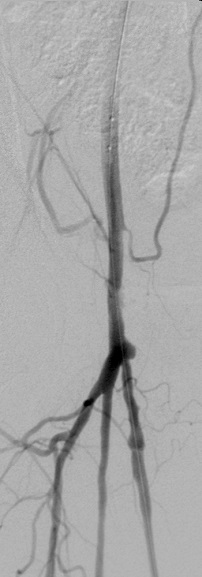

Eine Angiographie wird durchgeführt um Erkrankungen der Gefäße (Arterien und Venen) darzustellen und zu beurteilen. Hierzu zählen vor allem:

- Darstellung von Gefäßen (z.B. Hals- und Hirngefäße, Becken- und Beingefäße)

- Aussackungen von Gefäßen (Aneurysmata)

In der Regel wählt man als Zugang zu den Gefäßen die große Arterie oder Vene in der Leiste aus. Alternativ stehen weitere Zugänge in der Ellenbeuge oder am Handgelenk zur Verfügung. Nach einer lokalen Betäubung werden mit Hilfe von Führungsdrähten Katheter in die zu untersuchende Region vorgeschoben und von dort Kontrastmittel injiziert oder gefäßeröffnende (Gefäßstütze (Stent), Ballon, thrombenauflösende Medikamente, etc.) oder gefäßverschließende Maßnahmen eingeleitet. Diese Vorgänge werden am Monitor unter Durchleuchtung kontrolliert.